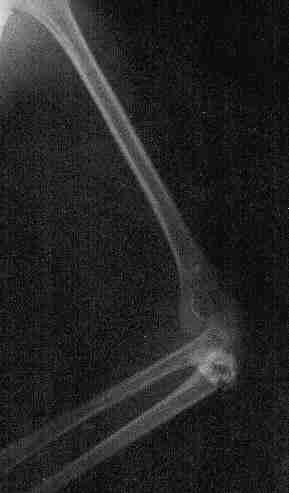

Fractura de codo izquierdo. Pablo, 4 años y medio La misma fractura, vista desde otro ángulo Reconstrucción del hueso (osteosíntesis) llevada a cabo tres días después Aspecto del hueso a los tres meses, después de retirar las piezas metálicas.

Fractura de codo izquierdo. Pablo, 4 años y medio

La misma fractura, vista desde otro ángulo